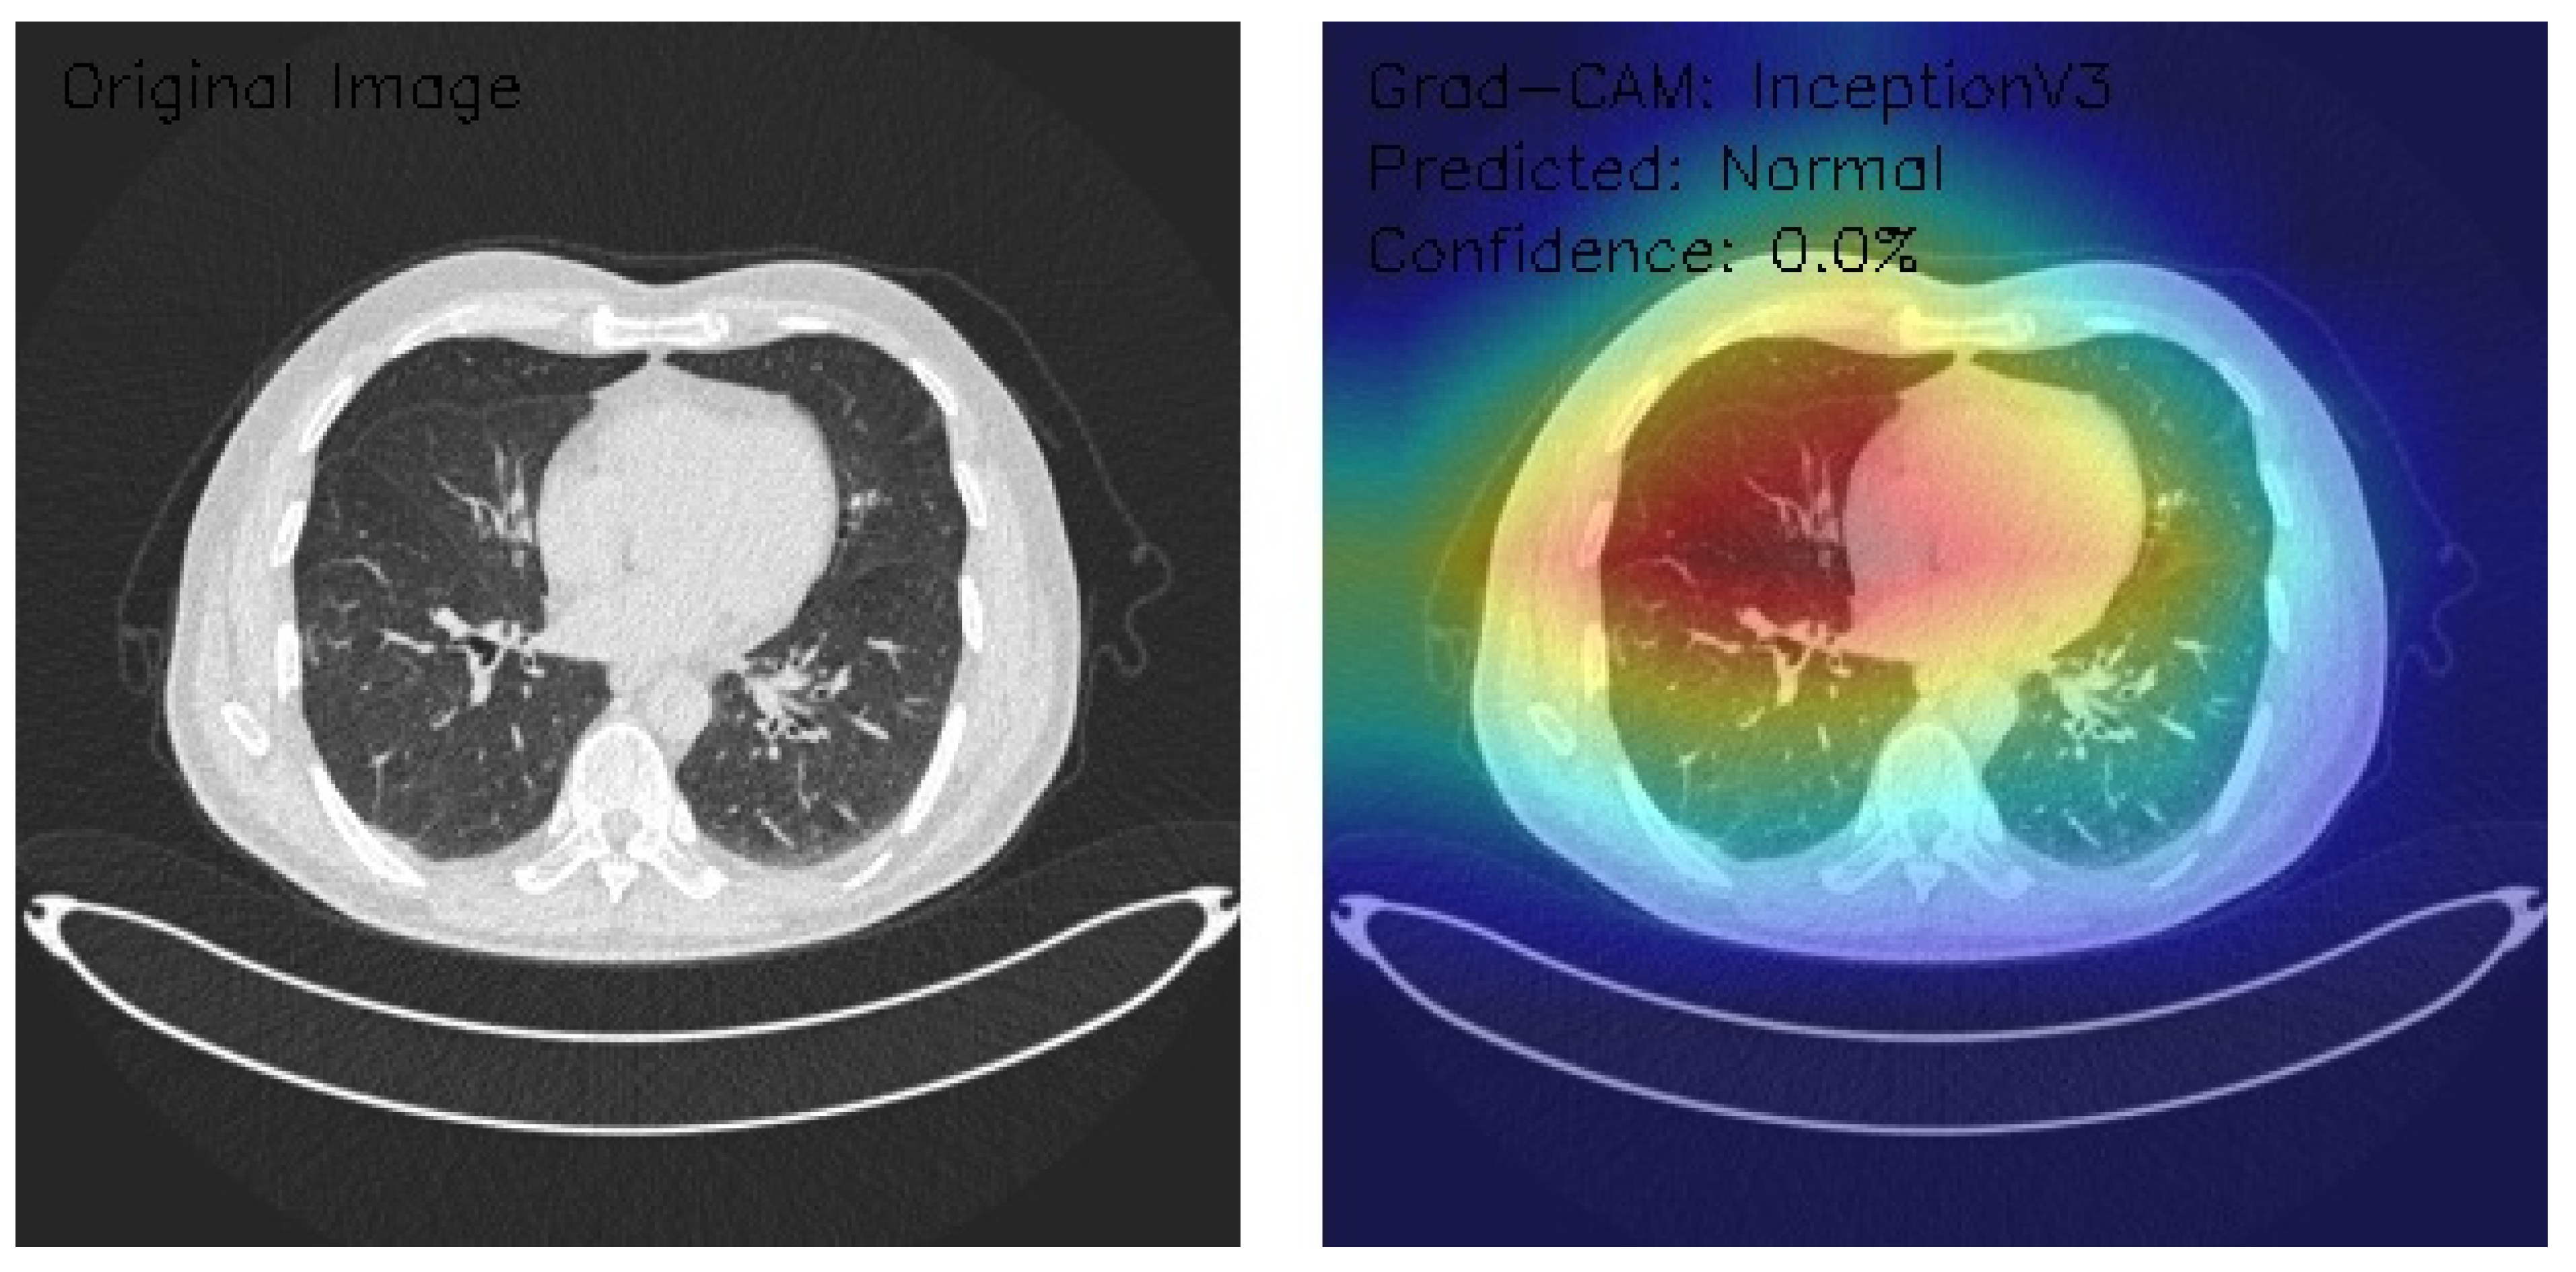

Analysis of InceptionV3 Model Performance on Lung CT Images with Grad-CAM Visualization

The results section of this study presents the detailed findings from an advanced analysis of three axial chest CT images processed using the InceptionV3 deep learning model. This analysis leverages the sophisticated capabilities of Grad-CAM to provide a comprehensive visualization of the regions within the CT images that the model identifies as significant for its predictions. Combining the robust classification performance of the InceptionV3 architecture with the interpretability offered by Grad-CAM, this approach not only evaluates the model’s predictive accuracy but also elucidates the spatial patterns of attention within the medical imaging context. This dual focus allows for a deeper understanding of the diagnostic potential of deep learning in radiology and the interpretive transparency essential for clinical application. The following results detail these observations, highlighting key insights into the model’s behavior and implications for automated diagnostic processes.

Figure 9 shows that the CT image reveals clear lung fields with well-defined bronchial structures, indicating no abnormalities in the original scan. The Grad-CAM visualization highlights a distinctive rainbow-like activation pattern, predominantly focusing on the central and bilateral lung fields with symmetric intensity. Despite these detailed attention patterns, the model classifies the image as Normal with a confidence score of 0.0%, pointing to significant issues in confidence calibration. This suggests the model can identify relevant anatomical regions but lacks reliability in translating these insights into confident and actionable classifications. Further calibration and optimization are necessary for clinical applicability.

Figure 9.

This analysis evaluates three axial chest CT images processed by an InceptionV3 model with Grad-CAM visualizations, focusing on attention regions and classification outcomes. Image 1 shows clear lung fields with symmetric central activation, classified as Normal with 0.0% confidence. Image 2, with scattered nodular opacities, displays peripheral activation patterns and is classified as Malignant, again with 0.0% confidence. Image 3 exhibits interstitial patterns with strong central and right-sided activation, also classified as Normal with 0.0% confidence. The Grad-CAM visualizations highlight relevant anatomical features, but the model’s uniform low confidence scores reveal calibration and classification inefficiencies. Recommendations include the recalibration of confidence scoring, fine-tuning classification layers, and integrating ensemble methods. While feature detection appears robust, these refinements are critical for clinical reliability and decision-making.